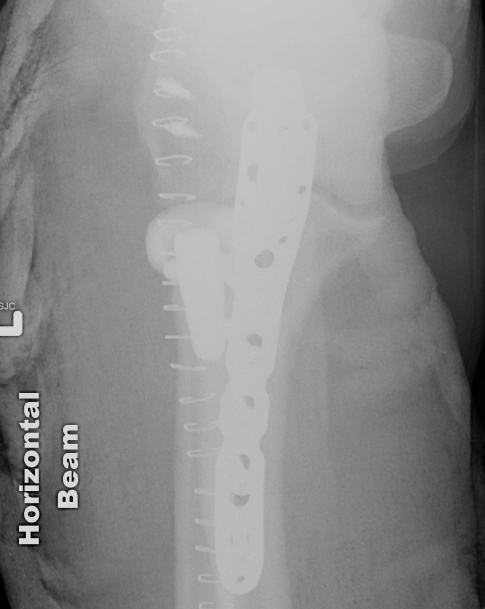

ORIF olecranon with plate +/- LCL repair

- posterior approach and plate olecranon

Olecranon plate + ORIF Type II coronoid process + radial head replacement

Olecranon plate with radial head replacement

Olecranon plate with radial head replacement + LCL repair

Olecranon plate + medial coronoid buttress plate + radial head replacement